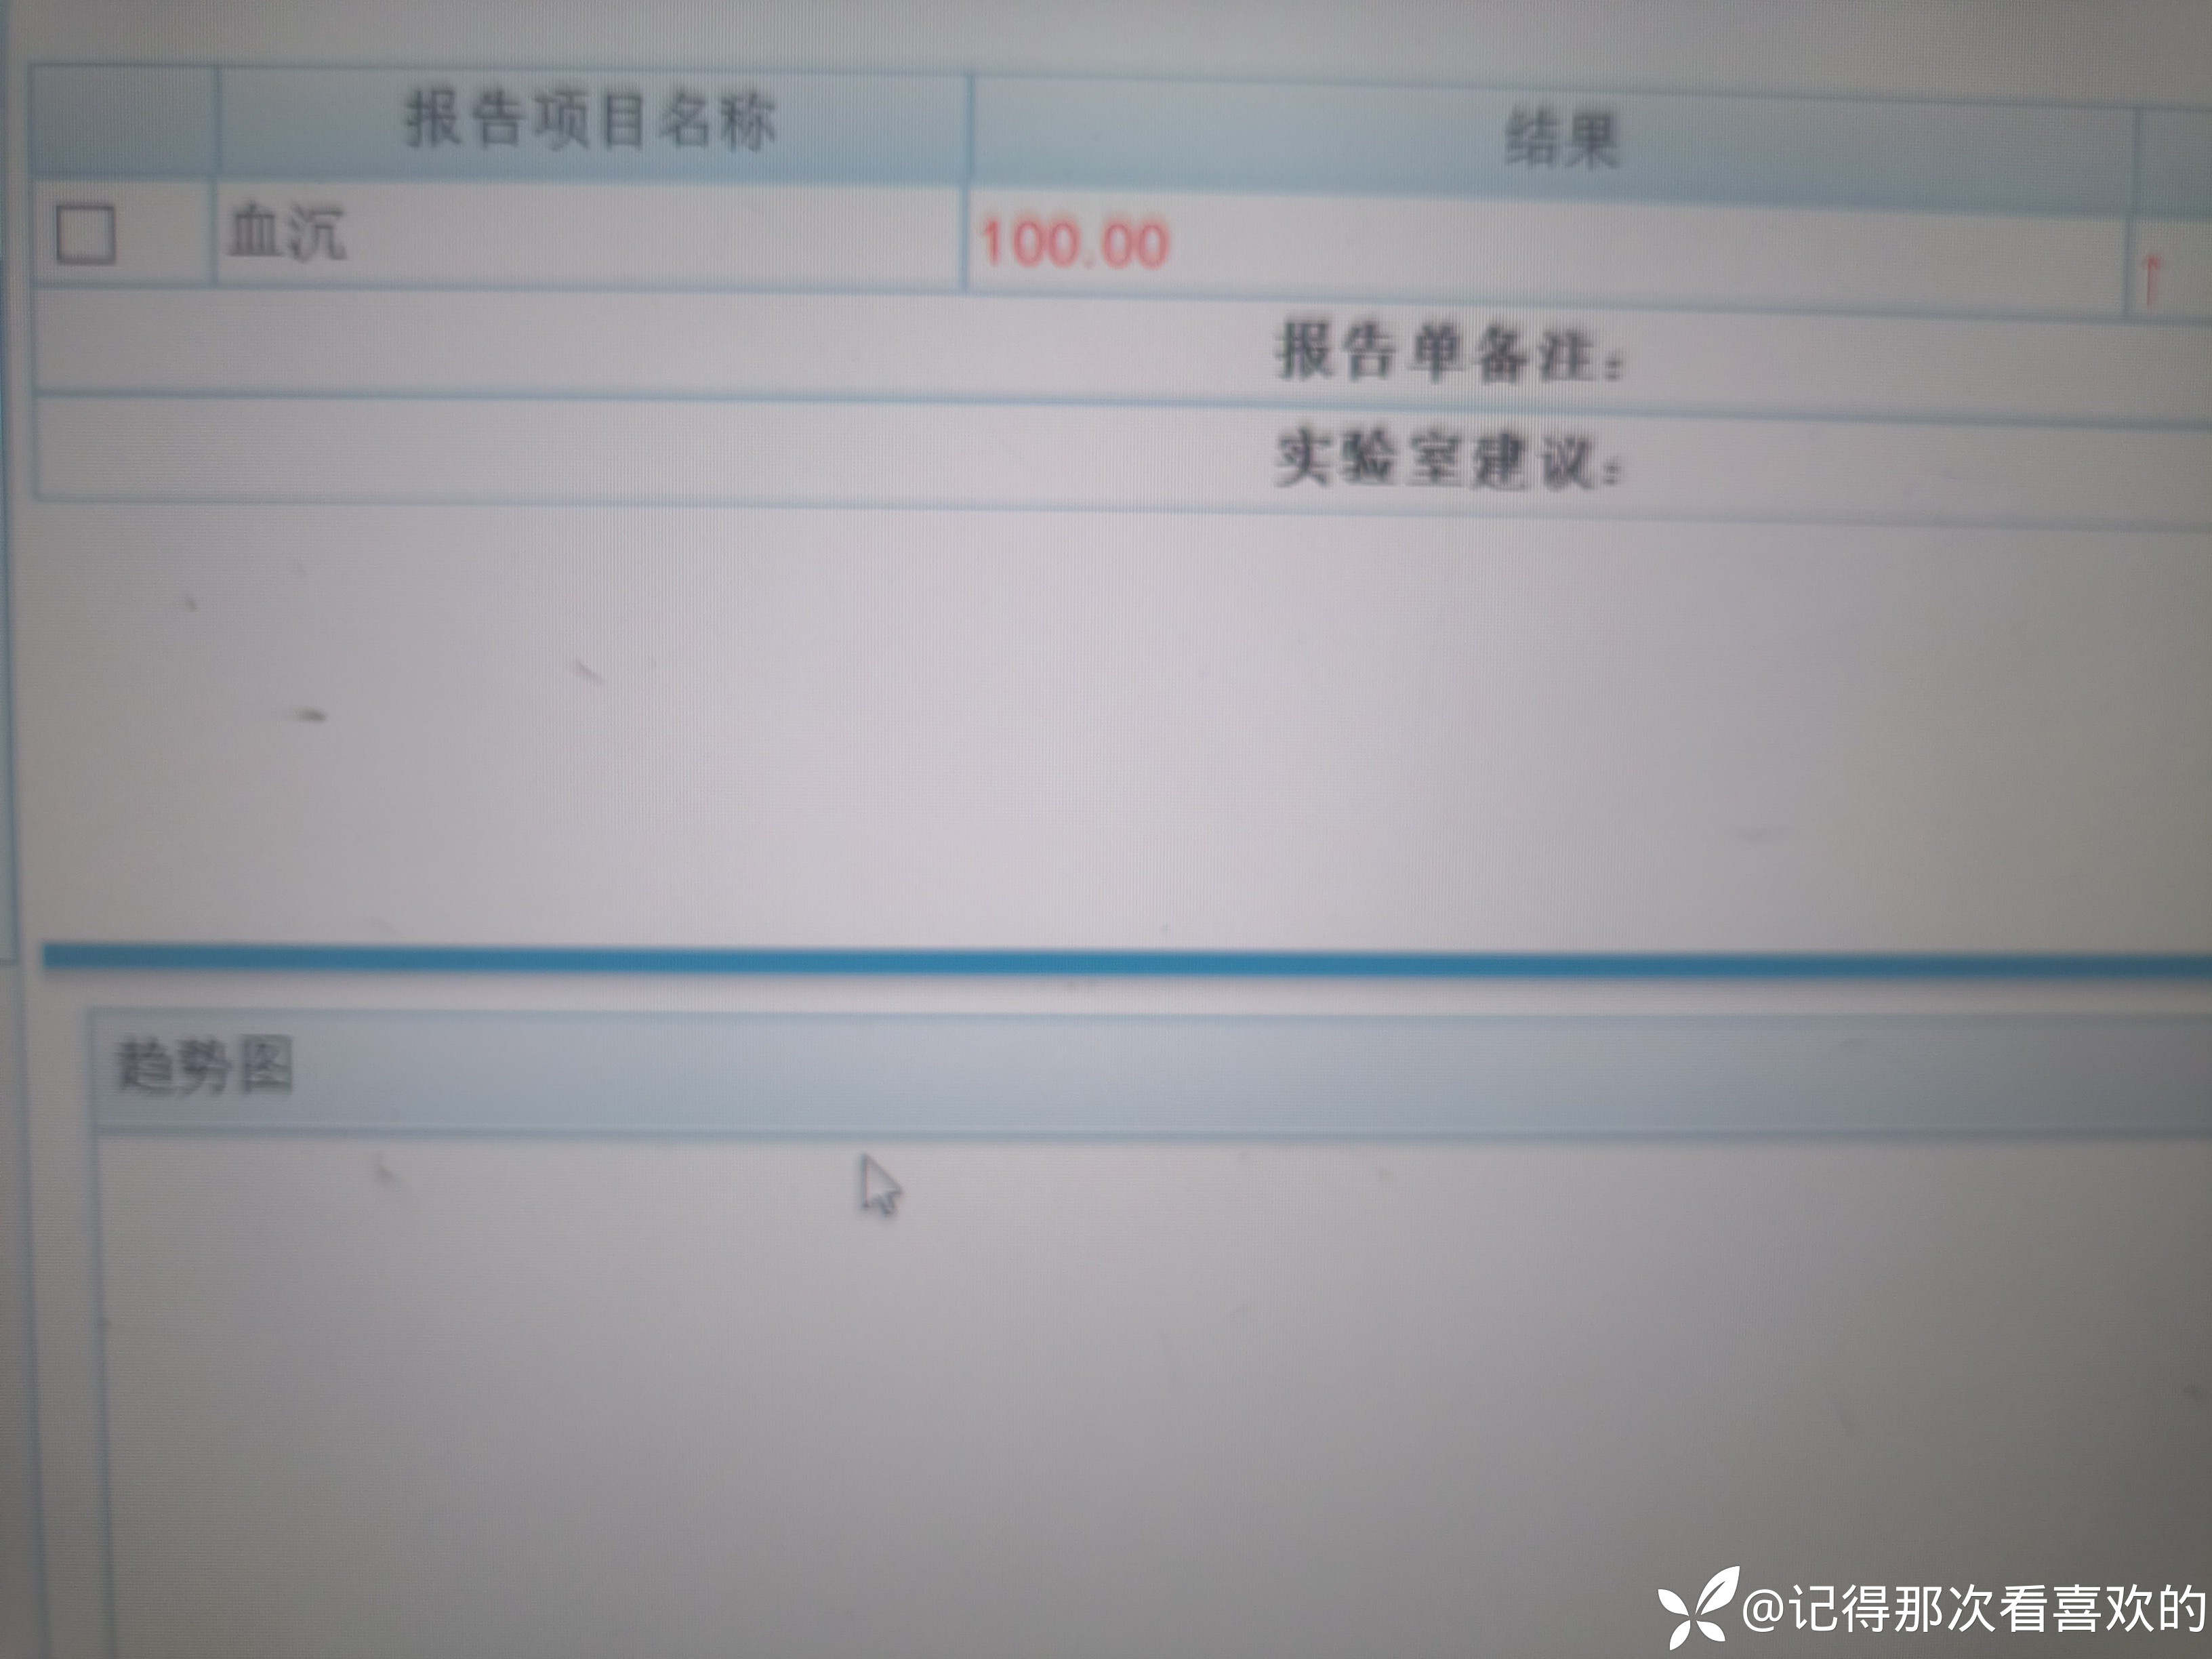

病例特点:患者钟某 男,14岁,以"髋、膝、足肿痛1年余,加重3日。"为主诉入院。现病史:缘于1年前无明显诱因出现左侧髋关节、双足跟、左踝关节、右足第一足趾关节肿胀、疼痛, 疼痛呈持续性,多于阴雨天、活动后症状加重,疼痛未向他处放射、转移,症状严重时行走困难。遂就诊于我科,查"HLA-B27(+)、CRP 70mg/L、骶髂MR:骶髂关节肿胀",诊断为"强直性脊柱炎",先后予皮下注射"司库其尤单抗150mg qw、阿达木单抗40mg q2w",上述症状较前好转,此后不规律用药,于半年前自行停用上述药物,未再规律随诊。3日前再发左膝、双肘关节肿痛,性质同前,程度较前加重,影响行走,伴有发热,体温最高达39℃,自行服用退烧药(具体不详)后体温较前下降,上述关节肿痛无明显改善。现为求进一步治疗,就诊我院,门诊拟"强直性脊柱炎"收住入院。体格检查:T36.6℃ P138次/分 R50次/分BP/120/68mmHg 专科情况:生命征平稳,神志清楚,双肺呼吸音清,未闻及干湿啰音,心律齐,各瓣膜听诊区未闻及杂音,全腹软,无压痛及反跳痛,未触及包块,双肘、左膝关节肿胀、压痛、触之皮温高。双下肢无浮肿,病理征未引出。

诊疗计划:1.入院予二级护理,监测血压、脉搏、呼吸。2.入院完善三大常规、凝血、生化、骶髂MR、彩超、CT、心电图等相关检查评估病情。3.治疗上暂予抗炎镇痛,辅以护胃治疗,待相关检查结果回报后进一步治疗,本次就诊拟行生物制剂治疗,予完善骨保护药物,传染病相关检查排除禁忌症,患者本次发病伴有发热达39℃,追问病史患者诉偶有干咳不适,目前已改善,予完善呼吸道病原学检查明确病情。4.患者Padua评分1分,属于发生VTE低危风险,实行VTE基本预防,动态评估Padua评分。5.已将目前病情及现有临床诊断以及存在疾病复杂性、个体的差异性、对治疗的反应不同、鉴于目前医学技术水平有限,和下一步相关诊疗详细充分告知患者家属,取得家属的理解并同意配合下一步诊疗及检查。6.NRS-2002评分3分,目前患者营养状态尚可,进食情况尚可,根据病情变化动态评估。